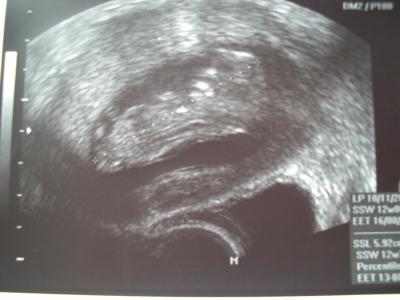

Dem Bauchzwerg geht es super. Herzchen hat fleißig geschlagen, geturnt hat es auch, Händchen, Füßchen, alles dran! Laut US wäre haute 12+3 (eigentlich 12+0), Gyn hat es auch nicht geändert. Kritische Zeit ist rum - puh endlich! SSL war 5,92cm Hach bin ich jetzt glücklich. Hoffe das jetzt diese blöde Übelkeit auch endlich mal nachlässt! LG Ina, mit fettem Grinsen im Gesicht.

Bild zu Zurück vom Doc :D - Forum für August - Mamis